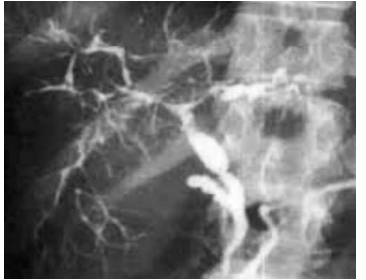

Uma paciente de 65 anos de idade apresenta desconforto na região do hipocôndrio direito, associado à icterícia. Refere colecistectomia há dois anos, após uma pancreatite aguda biliar. É portadora de lúpus, com controle feito com baixa dosagem de corticoide. Teve, há dois meses, covid-19 grave, recuperando-se bem (ainda com dispneia aos esforços médios). Realizou um ultrassom, que mostrou colédoco de 8 mm, sem sinais claros de litíase. Após exames laboratoriais confirmarem a elevação de bilirrubinas, gama GT, fosfatasse alcalina e transaminase, foi solicitada a colangiorressonância mostrada a seguir.

Com base nesse caso hipotético, é correto afirmar que se trata de